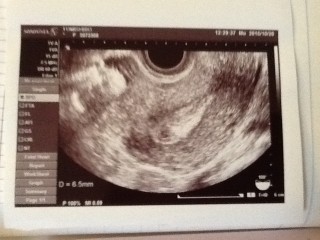

胎嚢7.3mmでした。

出血があり心配で初めてお医者さんに行ったら、超音波で胎嚢発見。 出血が多くなったらすぐに来てと言われ今は少なくなってきてるので来週にまた検査! 胎嚢が大きくなってれば来週におめでとうと言ってもらえます♪ 不安ばかりだけど、旦那が俺らの子供なら強いでしょと言っていたので、赤ちゃんを信じて一緒に頑張っていきます(*・з・*) 大きくなっているように赤ちゃんの生命と神様にお願いだ!あとは私も頑張らなくちゃ!

本日胎嚢を確認出来ました。